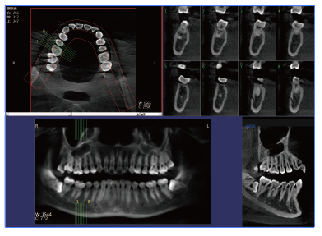

牙齿的健康越来越受到人们的重视,加上饮食因素的影响,往往会导致其患上口腔疾病的几率增大,因此,一旦出现口腔疾病问题,要做好口腔的检查,相比传统的CT检查,现在的口腔CBCT具备哪些优势?它们两者之间的对比来看,都分别具备哪些优势?

一、口腔cbct的优势1、射线剂量低,可广泛应用于口腔颌面外科,正畸科,正颌外科和种科等。

2、在视野选择上面,图像合成等口腔专业所学个性化的图像生成方面,口腔cbct的优势更为凸显,其发展空间较大。